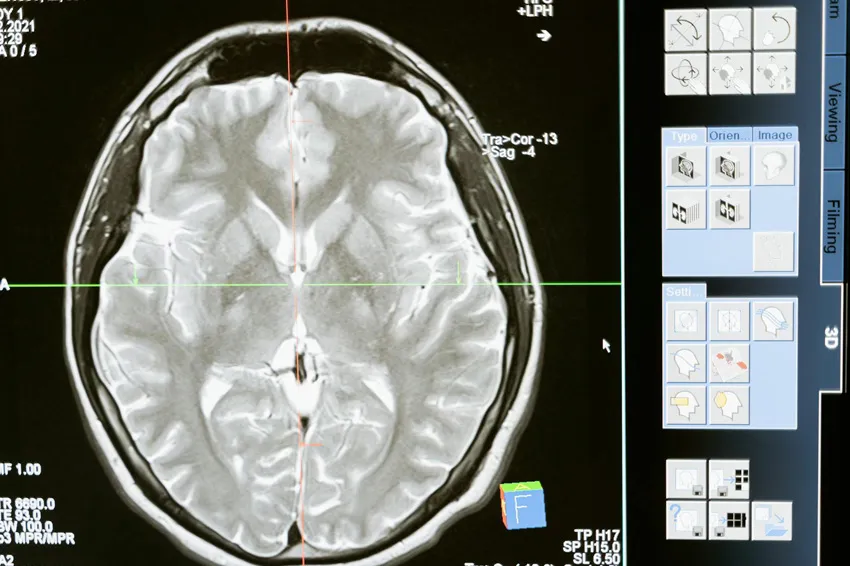

Understanding Brain Injuries

A brain injury can occur when the brain is damaged by trauma, lack of oxygen, disease, or another force inside the body. Some brain injuries heal over time — others change a person’s life forever.

There are two main categories of traumatic brain injury (TBI):

Closed-Head Injuries

The skull remains intact, but the brain is shaken or jolted inside the skull. Concussions are the most common type, but they can still be serious.

Open-Head Injuries

A foreign object penetrates the skull, damaging brain tissue. These injuries can be life-threatening and often require emergency surgery.